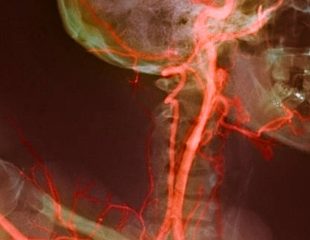

شریان کاروتید

بیماری سرخرگ کاروتیدی : دلایل ، علائم ، تست ها و درمان

به بیماری سرخرگ کاروتیدی تنگی سرخرگ کاروتیدی ، هم گفته میشود که باریک شدن سرخرگ کاروتیدی را به همراه دارد. ...